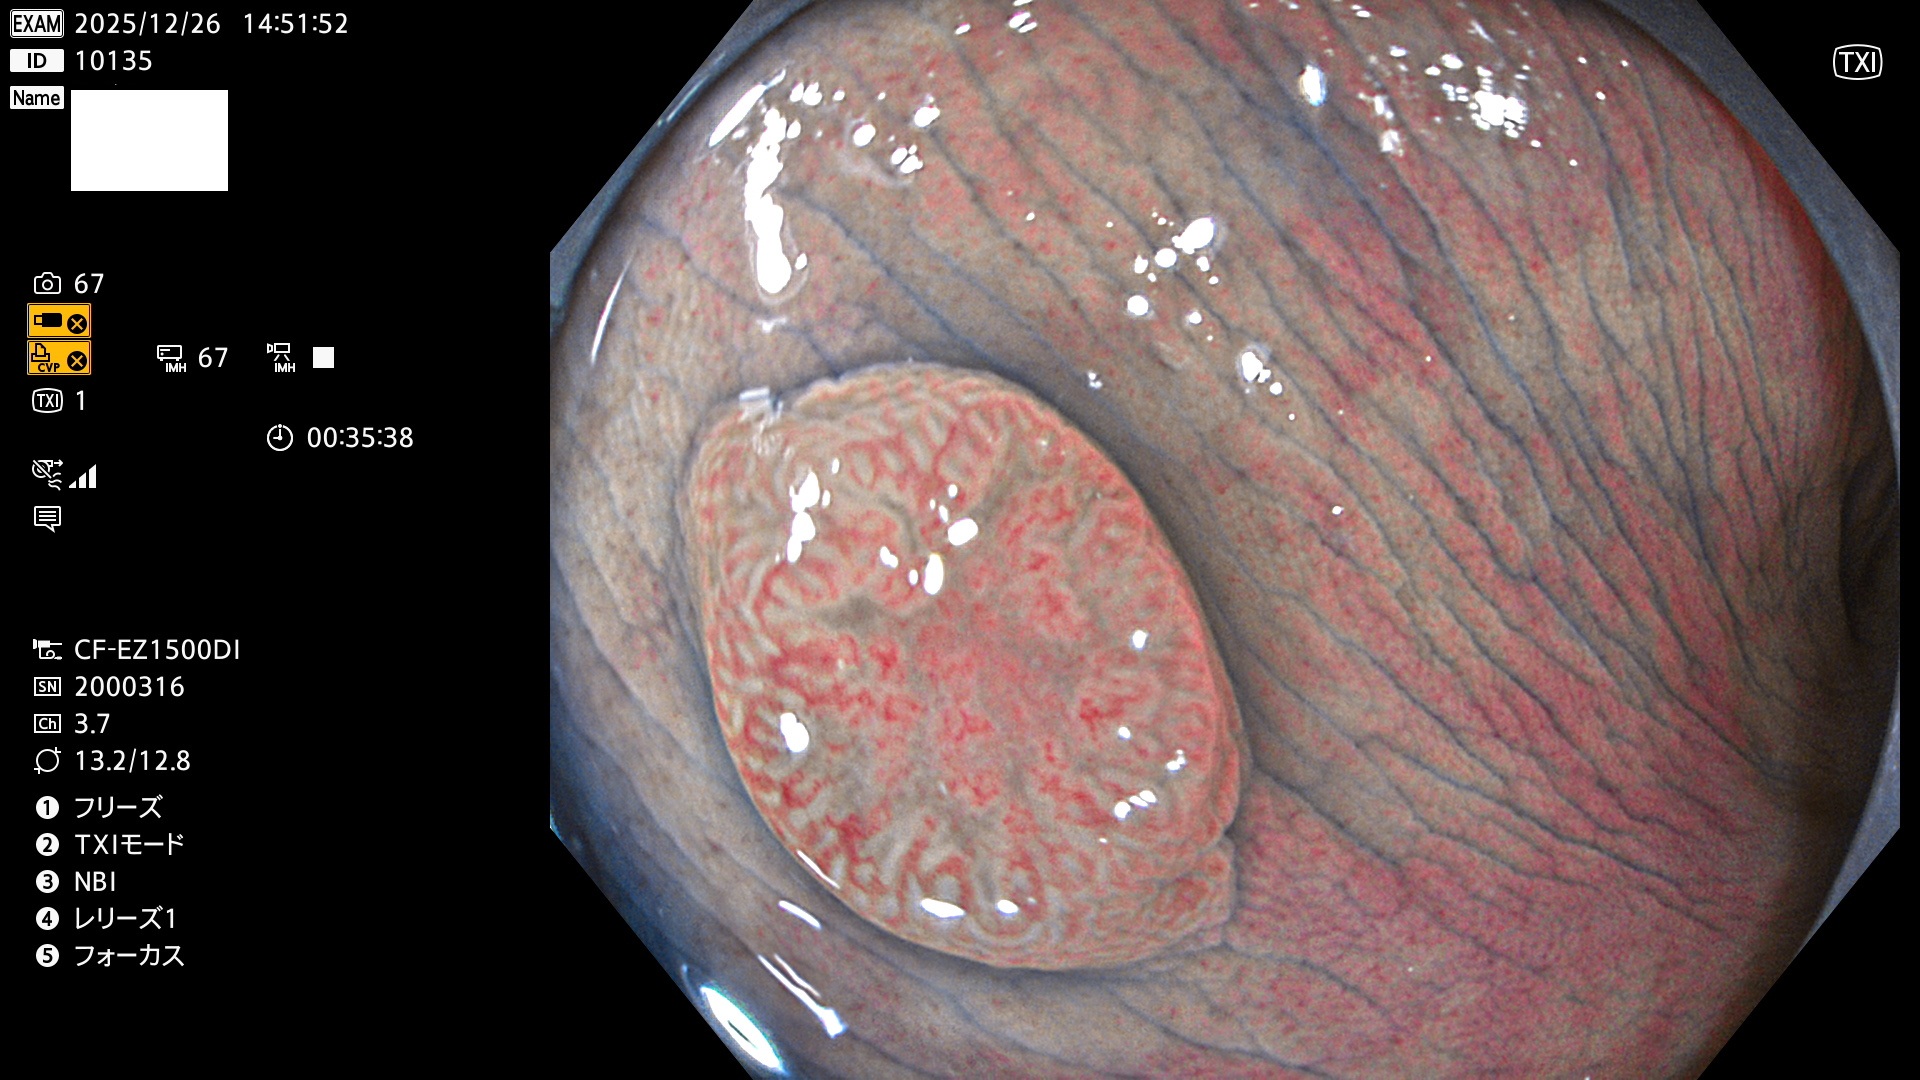

完全に平坦な物をUb、陥凹している物をUcと呼びます。Ubは認識が困難で、Ucはびらん(炎症)と紛らわしいために見落とされやすく、「内視鏡後・大腸癌」の原因になります。

毎週の検査(木・金・土・日)に発見されたUbとUc型・腺腫を、その週の日曜の夜にUPし1週間、提示します。

2025年12月18日〜12月29日の8日間(80件)13個 (Uc_ADR=13個/80人=16%)